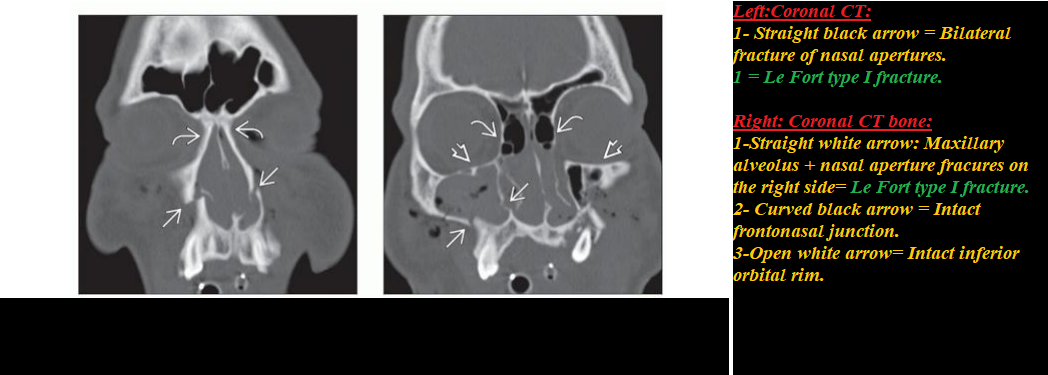

Head & Neck Emergency:Diagnostic Imaging (Click on image to magnify). Get link Facebook X Pinterest Email Other Apps - February 08, 2020 Get link Facebook X Pinterest Email Other Apps Comments